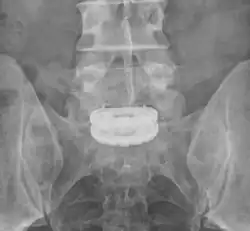

Die Abbildung zeigt einen Zustand nach Spondylodese der zwei untersten Lendenwirbelkörper (LWK4 und LWK5) mit dem ersten Sakralwirbel (SWK1) zwei Jahre nach der Operation. Der Zwischenwirbelraum zwischen dem vierten und dem fünften Lendenwirbelkörper ist bereits knöchern überbrückt (ankylosiert); beim Übergang vom fünften Lendenwirbelkörper zum ersten Sakralwirbel fehlt diese knöcherne Durchbauung. Wenn alle verblockten Wirbelkörper stabil knöchern miteinander verbunden sind, kann das Spondylodesematerial entfernt werden.

-

Dorsoventrale Spondylodese LWK5 – SWK1 -

Der gleiche Patient in der MPR -

Die Pfeile zeigen die knöcherne Durchbauung LWK4/5 und die fehlende Durchbauung LWK5/SWK1 an. -